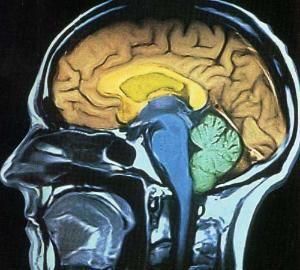

任務控制

大腦丘腦下部的下丘腦視交叉上核或生物鐘保持身體隨著24小時的節奏運轉。生理節奏引起的一個最明顯的結果是:睡眠-醒來的循環,但是生物鐘還影響著消化力、體溫、血壓和激素的產生。研究人員發現,通過增強光亮調節褪黑激素可以將生物鐘向前或向後調整。最近人們不斷爭論,是否可以通過補充褪黑激素來幫助人們預防飛機時差——昏昏欲睡和飛機通過時區時產生的頭痛感。

人生的某些經歷很難忘卻,科學家利用大腦成像技術設法弄清楚創造記憶和儲存記憶的機械反映。發現大腦灰質內部的海馬體能充當記憶儲存箱的功能。但是這個儲存區域的分辨能力並不強。對相同的大腦區域的刺激,可以讓它產生真實的和虛假的記憶。為了把真實記憶從虛假記憶中脫離出來,研究人員提出根據背景回憶以加強記憶的方法,如果某些事情沒有真正發生過,就很難通過這種方法加強人腦對它的記憶。